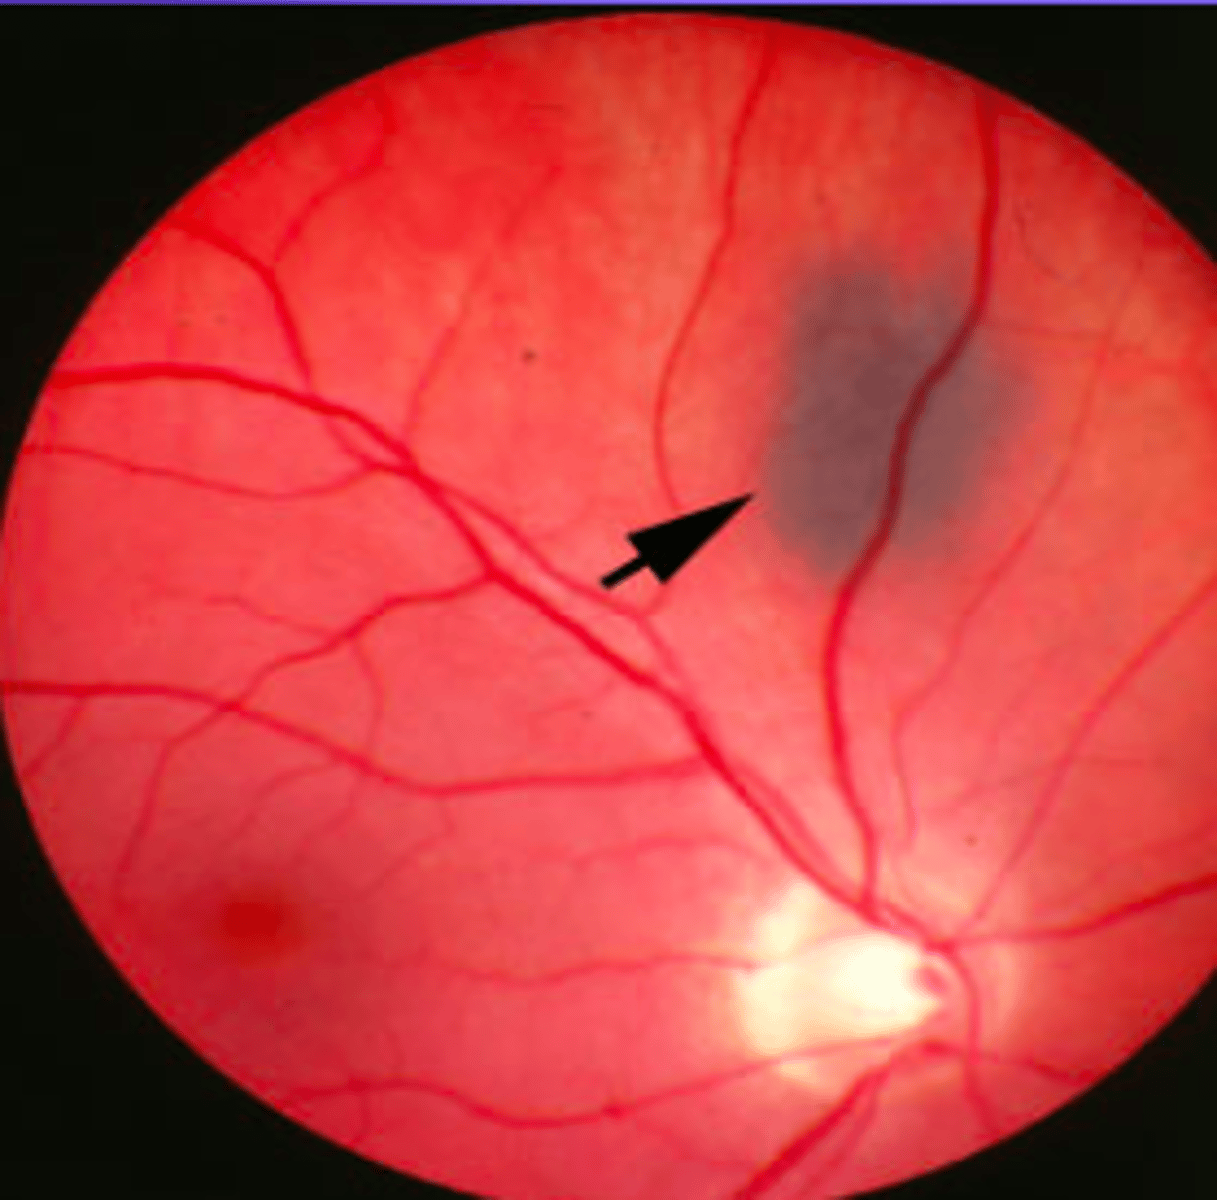

Cystoid degeneration aetiology

Present in ~100% of eyes over 80 years of age (increases with age)

• Tiny vesicles with indistinct boundaries on a greyish-white background

• Usually close to the ora serrata

• May resemble lattice degeneration -cystoid is elevated while lattice is

depressed

• Benign (although possible link with degenerative retinoschisis)